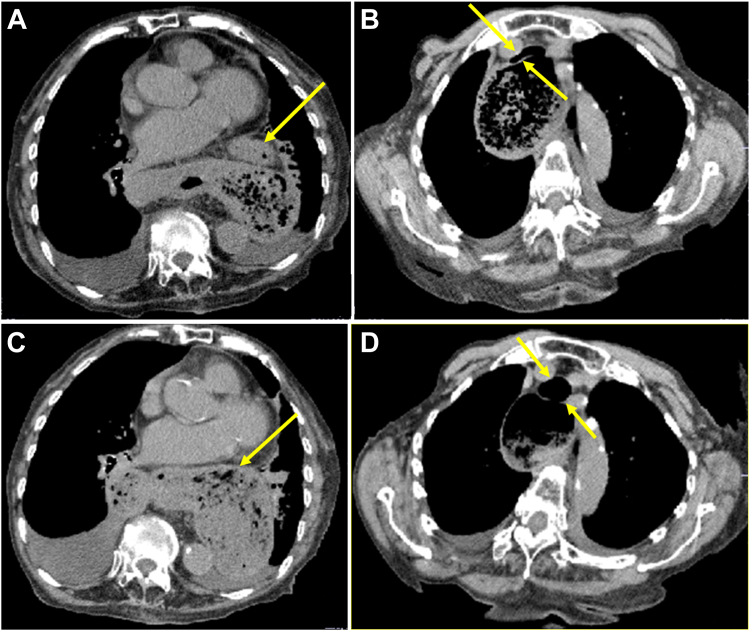

Recurrent Respiratory Distress Caused by Temporary Herniation of Transverse Colon Into Hiatal Hernia in Patient With Kyphosis

后凸患者暂时性横结肠疝入裂孔疝引起复发性呼吸窘迫。